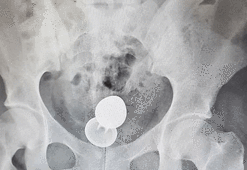

Fantezi hastanede son buldu!

Fantezi hastanede son buldu!İngiltere'nin Sussex bölgesinde yaşayan genç bir kızın başına utanç verici bir olay geldi. Partneriyle cinsel hayatını renklendirmek için seks oyuncağına başvurunca hayatının pişmanlığını yaşadı. Fantezi hastanede son buldu.